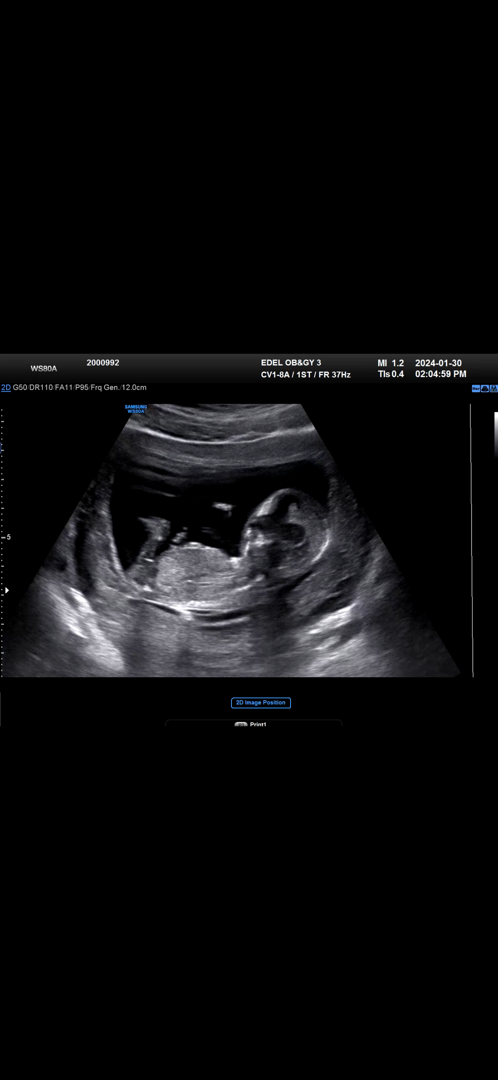

13주 초음파 각도법 한 번 봐주세요❣️

첫째때는 이렇게 안 궁금했는데 둘째니깐 너무 궁금해요ㅠㅠ 자매일까요? 남매일까요?!